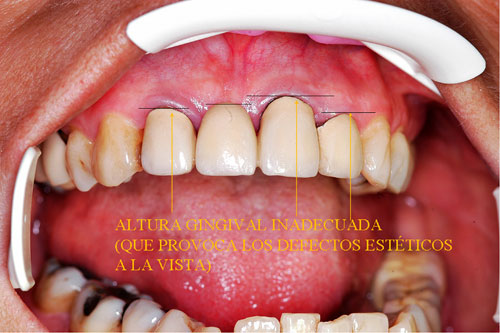

RESUMEN Mostración del Protocolo en R. O. y su desarrollo clínico. DESARROLLO Quienes realizamos Rehabilitación Bucal Integral desde muchos años atrás, siempre hemos buscado un protocolo coherente que nos permitiera ordenar el pensamiento cuando nos encontramos con aquellos caóticos casos donde marearse en la resolución es fácil y frecuente. PROTOCOLO DE ALONSO Sintéticamente consiste en otorgar al Sistema en primer término: Desoclusión en Lateralidades y Propulsiva de los sectores posteriores, mediante la construcción de la Guía Anterior tanto en los Provisorios como en los Definitivos, basados en el Encerado de Diagnóstico. PROTOCOLO PRÁCTICO (BASADO EN D.A.T.O.) Diagnóstico: clínico, radiográfico (donde no es necesario extenderse) y de laboratorio, donde mediante un encerado diagnóstico y otro de trabajo, conoceremos la fiel réplica de la boca del paciente antes de destruirse y los medios para reconstruirla basados en los procedimientos que podemos realizar en la cera. PRESENTACIÓN DEL CASO Se presenta la paciente derivada por un compañero a fin de consultar acerca de un primer molar superior izquierdo, a quien el Periodoncista aconsejaba realizar una radectomía debido a la pérdida ósea distal que dicha raíz presentaba. Dicha observación hace que decidamos tomar una actitud más conservadora, explicando al enfermo las razónes etiológicas de la pérdida ósea, y aconsejando quitar dicha funda para colocar una provisional morfológicamente correcta, y simultáneamente re-endodonciar y realizar la terapia básica periodontal. Visión Global del Caso Se observa a la inspección clínica y radiográfica, varios puentes fijos filtrados, como así también amalgamas de plata recidivadas. Inversión de la Curva de Wilson.(2º Elemento a nuestro alcance para obtener Desoclusión Se procede entonces luego de realizar los correspondientes modelos de yeso mediante impresiones precisas de alginato con cubetas Rim Lock, a tomar un registro cráneo maxilar mediante un arco facial estático (Artex) que nos permita montar el modelo superior respecto del Plano de Frankfurt con el punto Gnation de referencia. Luego, haciendo uso de las Laminillas de Long , (buscar referencias en el libro del Dr. Alonso o bien en múltiples publicaciones personales en Gaceta Dental o Maxillaris, como así también en mi propia web: en los artículos : RELACIÓN CÉNTRICA o AJUSTE OCLUSAL, BASES FILOSÓFICAS DE UNA OCLUSIÓN ORGÁNICA), (www.dracuna.com o www.oclusión.es,) . Procedemos a obtener el Registro Inter Maxilar de OCLUSIÓN EN RELACIÓN CÉNTRICA, mediante el cual, montamos el modelo inferior respecto del superior. Montamos así, en un Artex totalmente ajustable, pués no contábamos en ese momento con ningún semiajustable disponible,(ya que estaban todos ocupados), ajustando el Ángulo de Bennet y la Inclinación de la Trayectoria Condílea en gradaciones personalizadas mediante registros de Propulsión y Lateralidades). Procedemos entonces al estudio de los modelos. DIAGNÓSTICO GENERAL Disfunción oral generalizada, provocada por alteraciones en la Oclusión, en la Operatoria Dental, en la Endodoncia, en la Periodoncia y en la Prótesis realizada en esta boca a través de los años. Filtración generalizada de fundas. DIAGNÓSTICO PROTÉTICO OCLUSAL Carencia de guía canina. Carencia de alineación tridimensional en guía anterior. Carencia de curva de Wilson. TRATAMIENTO SUGERIDO 1-Encerado Progresivo de Diagnóstico y Trabajo de Peter K. Thomas. HEMOS OBTENIDO: D.AT.O Hasta aquí, hemos solo observado los elementos de diagnóstico clínicos, radiológicos y de laboratorio, como para comenzar a trabajar. AUTOR: Colaboración: CASO PRESENTADO EN LAS SESIONES CLÍNICAS DEL ILTRE. COLEGIO DE DENTISTAS DE MÁLAGA. Ratificación del Protocolo en Rehabilitación Bucal a pesar de las incidencias propias de cada caso clínico. A propósito de un caso.

Los tejidos paradenciales muestran una recesión múltiple en todos los cuadrantes, estando tratada por el Periodoncista mediante raspajes y curetajes.

Carencia de Anatomía Coronaria

Canino que no cumple su Función Desoclusiva

Incisivo que no cumple su Función Desoclusiva